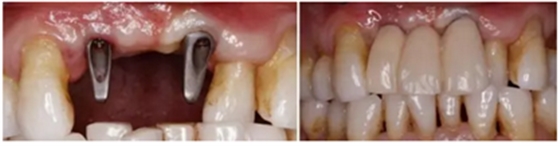

(4)3-shape數(shù)字化口掃進(jìn)行數(shù)據(jù)采集及最終修復(fù)體制作

(5)個(gè)性化基臺(tái)及臨時(shí)修復(fù)體戴入,軟組織成形

(6)最終修復(fù)體戴入